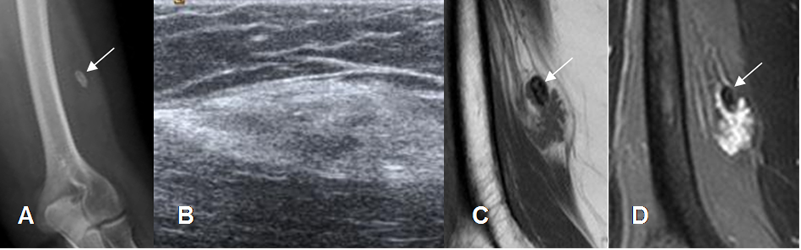

La apariencia con la RM, depende del tiempo de evolución. En las fases iniciales es similar a otra lesión muscular y en las tardías existe edema muscular, rodeando las imágenes hipointensas, que corresponden a calcio o fibrosis densa. (2). (Fig 31 y 32).

Fig 32. Miositis osificante.

A: Rx de brazo. Calcificación de tejidos blandos, en la parte lateral.

B: Ecografía longitudinal. Imagen ovalada, ecogénica y de tejidos blandos, dentro de las fibras musculares.

C: RM coronal en T1 y D: RM coronal en STIR. Imagen ovalada dentro del músculo vasto externo, hipointensa en T1 e hiperintensa en STIR, con calcificación gruesa hacia la parte superior (Flecha delgada), compatible con miositis osificante.